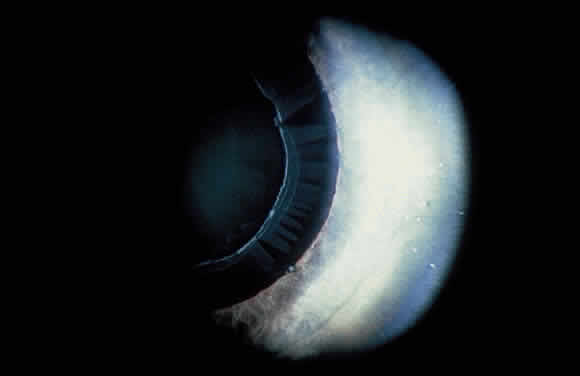

Deposition of exfoliative material on the anterior lens surface is the most commonly recognized feature of XFS and usually is best appreciated after pupillary dilation.43 A bull's-eye pattern generally is seen in which a translucent central zone and a granular peripheral zone of deposition are separated by an intermediate clear zone (Fig. 1). The translucent central zone of exfoliative material varies in diameter and may exhibit curled edges. In approximately 20% of patients with exfoliation, the central zone may be absent.38 The intermediate clear zone presumably results from lens contact with movement of the iris. The granular peripheral zone, which may be subtle but invariably is present in XFS, generally exhibits a well-delineated inner border and often shows numerous radial striations (Fig. 2). Occasionally, a bridge of exfoliative material may cross the clear zone to join the central zone and the granular peripheral zone.38,44